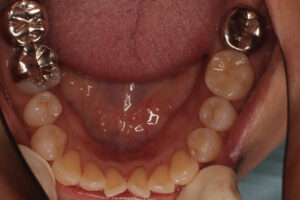

口腔内写真で明らかに違いが判るのは

保険で銀歯→ 自費で白い歯→

レントゲンでは神経の詰め物の状態の違い→